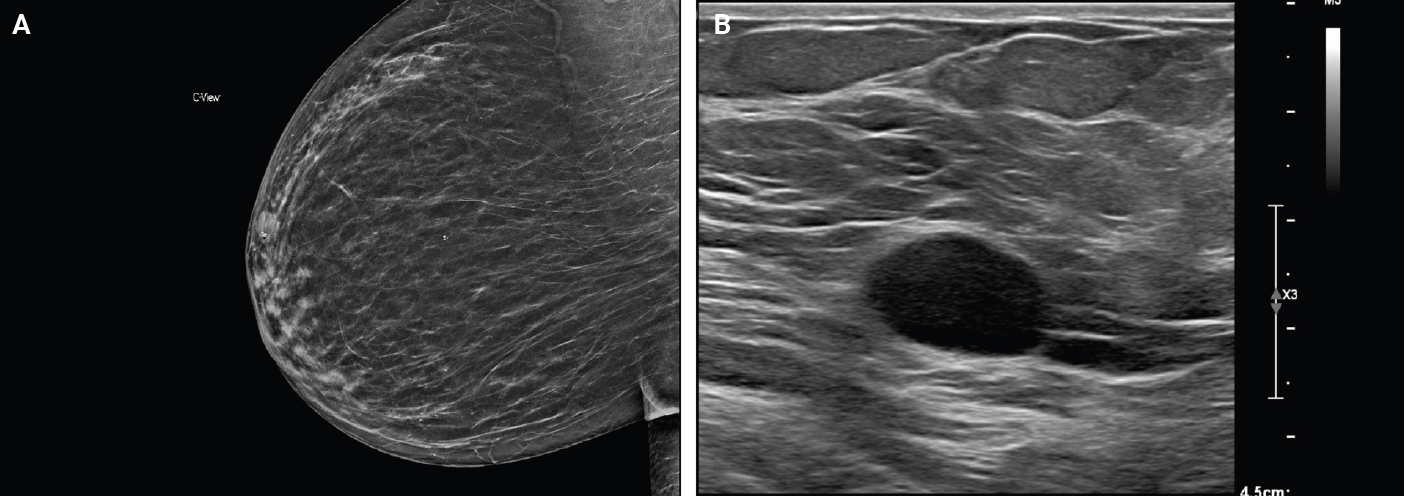

- Microscopically, breast schwannomas are well-circumscribed or encapsulated and can have prominent nodularity (Fig. 3A). Classic schwannomas have a bland spindle cell proliferation with various degrees of anisonucleosis, and wavy, elongated nuclei with tapering ends. These are arranged in parallel rows (nuclear palisading), also known as Verocay bodies (Fig. 3B). There is an abrupt transition between hypercellular (Antoni A) and hypocellular areas (Antoni B) (Fig. 3C). Antoni B areas have loose and myxoid stroma (Fig. 4A). Other key features to schwannomas include numerous small to medium sized vessels with prominent hyalinization and thrombi inside the lumen (Fig. 4B) and may also contain areas of hemorrhage or hemosiderin deposition [3,19].

- Immunohistochemistry is often needed to diagnose schwannomas, especially with small core tissue samples in the breast. The two most important positive stains are S100 (Fig. 4C) and SOX10, which are strong and diffuse in Schwann cells [3]. Schwannomas can also be positive for CD34 (weak, variable), calretinin, CD56, CD68 [21], podoplanin and Type IV collagen [22]. Classically, these are negative for estrogen receptor (ER), progesterone receptor, human epidermal growth factor receptor 2, smooth muscle markers (smooth muscle actin, desmin) and epithelial membrane antigen (capsule/perineurium only) [3]. Cytokeratins are generally negative, but may have rare labeling [23].

Fig. 4.Core biopsy of breast schwannoma with myxoid loose stroma (A), variably sized hyalinized vessels with intraluminal fibrin thrombi (B) and diffuse nuclear and cytoplasmic S100 reactivity in lesional Schwann cells (S100 immunohistochemistry) (C).